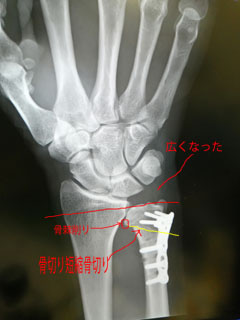

術前

術後

術後、尺骨短くなっているの分かるかと思います。

斜めに骨切り(黄色い線)

術前は、3mm短くすると言われましたが

術後に何ミリに切ったのか忘れてて聞いてなかったわ。

でも、突き上げ解消され良かったです。

橈骨と尺骨の間の尺骨の端の尖った骨棘も削ってました。

骨棘が当たって痛みでてるから削ると昨年末に言われてました。